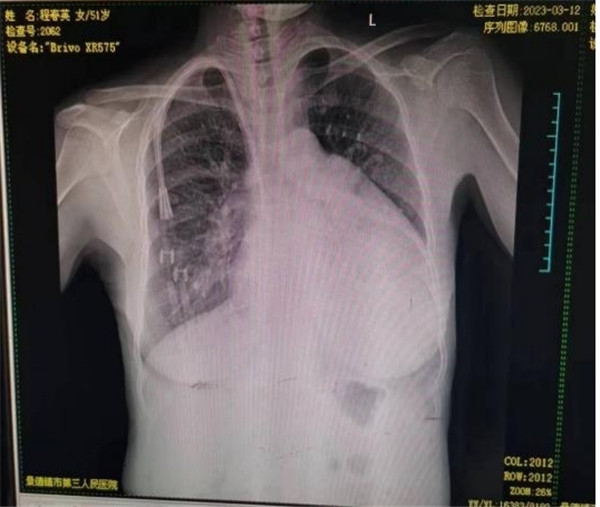

患者程某某,女,51岁,维持性血透8年余,长期血透导管功能障碍1月余。患者近1个月长期血液透析导管动脉端血液无法进出,血液透析时血液回流使用自身非内瘘静脉,导致患者透析不充分,病情加重,且血液透析困难,在外院拔出血透管失败,患者慕名来市三院肾内科就诊。

患者在行手术过程中长期血液透析导管无法拔除,行右颈内静脉、中心静脉DSA造影术,未发现明显狭窄,考虑血透导管与上腔静脉内壁、心房内壁黏连。